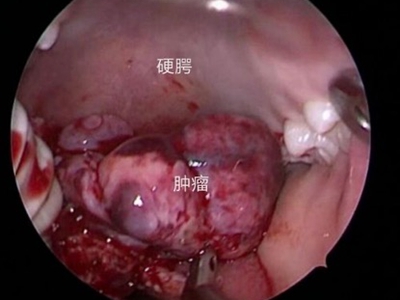

鼻咽纤维血管瘤又名“男性青春期出血性鼻咽血管纤维瘤”,是起源于鼻咽部的良性肿瘤,好发于14-25岁的男性青年,在鼻咽部的良性肿瘤中居首位。侵犯周围组织的能力较强,随瘤体的不断增大,易扩展到眼眶、鼻腔,甚至颅内,导致严重的并发症。

3、其他症状:肿瘤压迫咽鼓管,引起耳鸣、耳闭及听力下降。肿瘤侵入邻近结构则出现相应症状,如侵入眼眶,则出现眼球突出,视力下降;侵入翼腭窝引起面颊部隆起;侵入颅内压迫神经引起头痛及其他颅神经瘫痪。

鼻咽纤维血管瘤以手术切除为主要治疗方式。围手术期需要进行血管栓塞,术中控制低血压等。少数不能立即手术的患者,可酌用放射治疗、注射硬化剂、内服激素等治疗,等待手术时机。